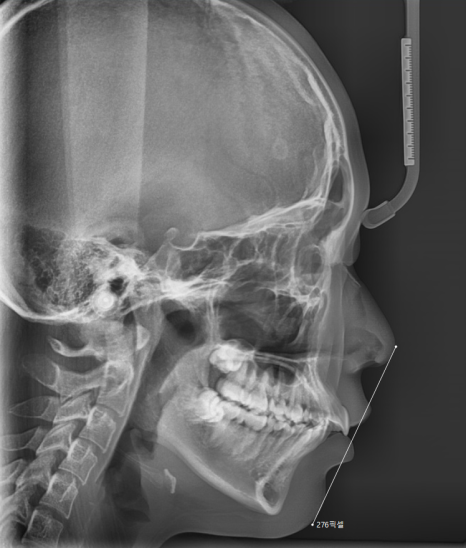

2단계: 정밀 검사 (X-ray 촬영 및 구외 사진)

얼굴 옆 모습을 찍는 x-ray도 찍고

증명 사진 찍듯 얼굴 모습도 기록해두죠.

정확한 검사를 위해 머리띠를 쓰고 찍을 때가 있는데

환자분들이 싫어하시더라고요ㅠㅠ